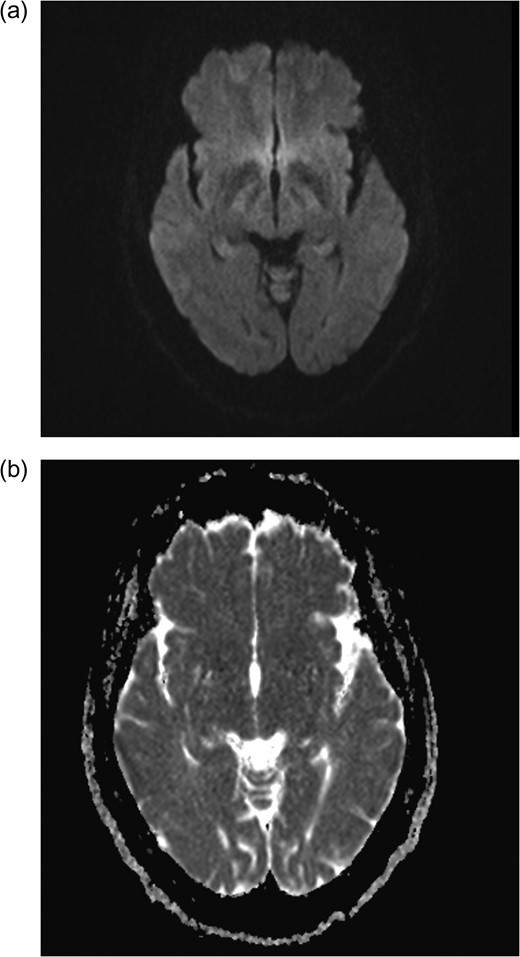

Axial MRI brain (a) diffusion weighted imaging (DWI) and (b) apparent diffusion coefficient (ADC) demonstrating no restricted diffusion.

It was reasonable to entertain an association with CHIKV as one sought to elucidate the cause of her seizures after 7 decades. Her case differed from those reported by Ganesan [10] in that she had seizures more than one year following diagnosis of CHIKV, normal EEG and CSF analysis, and she did not deteriorated unlike his first case. Additionally, he reported bilateral contrast enhancing frontal T2WI changes with restricted diffusion. She had resolution of the initial abnormality seen on T2WI/FLAIR sequence without steroid administration.